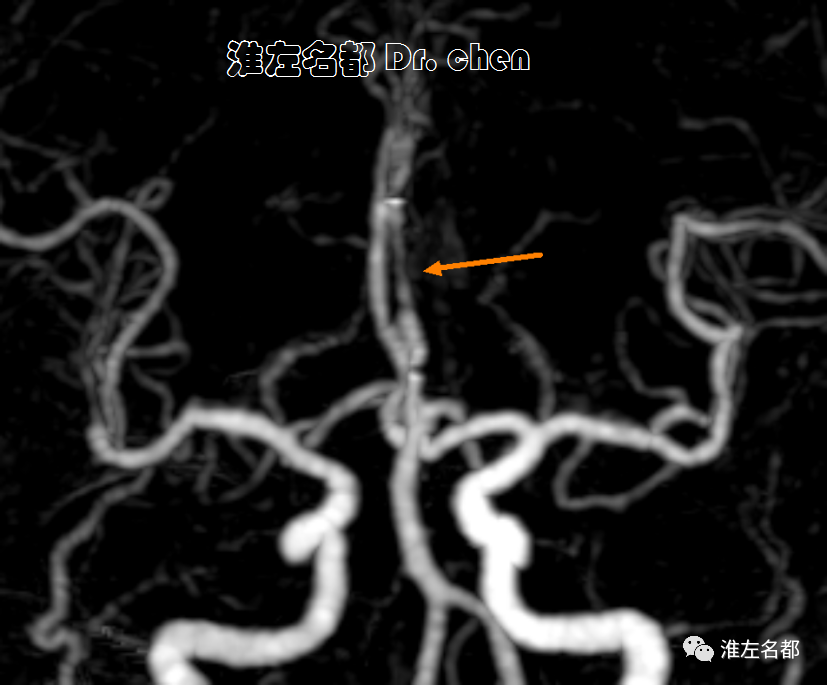

△颈部CTA:左侧颈内动脉颅外段螺旋样延长迂曲(白箭)。

△采用同轴技术将6F长鞘(90cm,Cook)送至左侧颈总动脉,造影:左侧颈内动脉颅外段螺旋样延长迂曲,经.035”泥鳅导丝将中间导管(Navien 072, 105cm)头端送至岩骨段(黑箭)。